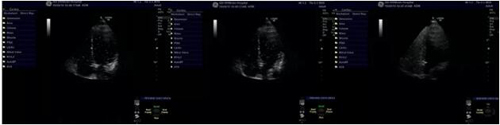

入院后完善相关检查,DWI显示多发脑梗塞;右心声学造影检查回报:右心声学造影阳性(大量RLSIII级),不排除卵圆孔未闭。

我院右心声学造影影像